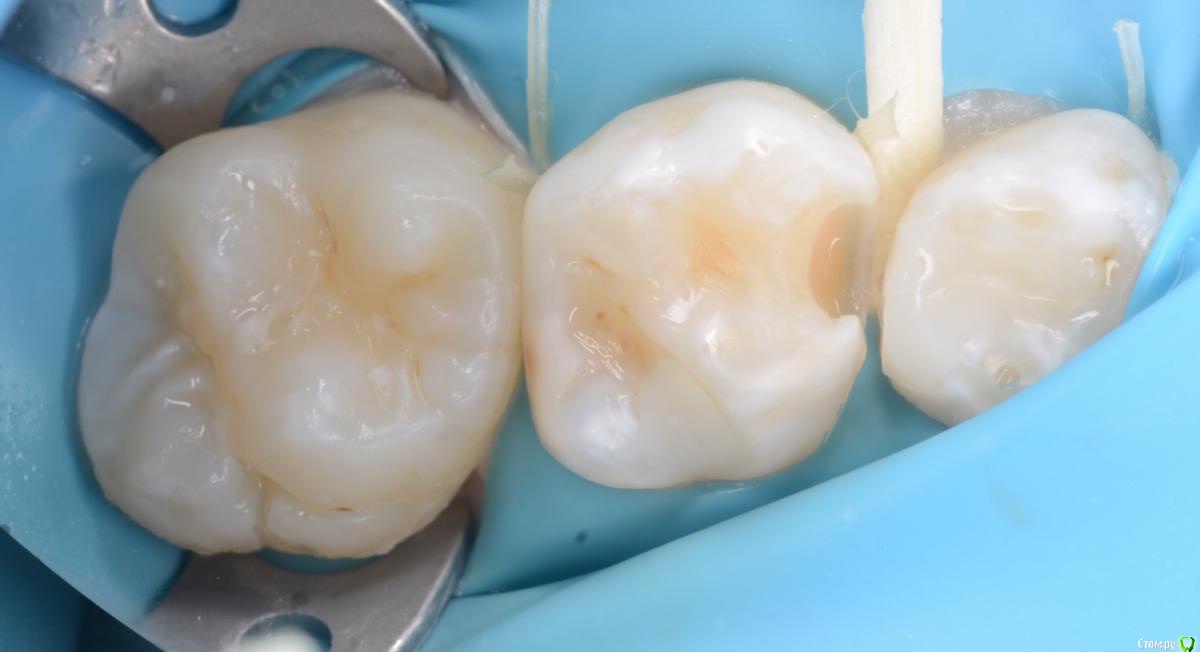

CRAZYDUCK Опубликовано 14 июня, 2018 Автор Поделиться Опубликовано 14 июня, 2018 Очередная история про скрытый кариес . Все зубы пролечили и успокоились . Пропали на год -два . А кариес растёт и радуется . Коллеги ,часто так бывает ? Часто . Но не в этом случае . Осмотр спустя 7 месяцев помог выявить скрытую кариозную полость на 5.5 зубе . RVG ( хочу diagnocam Ссылка на комментарий